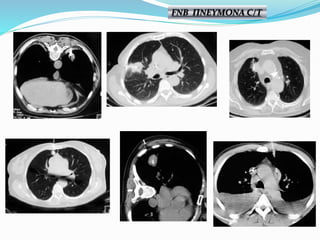

FNB ΠΝΕΥΜΟΝΑ C/T

Πνευμοθώρακας 11% Αιμορραγία 5% Αντίδρασηαπό το πνευμονογαστρικό <1% Τρώση μεσολοβίου < 1% Θάνατος ~ 0,02% Μετάσταση στην πορεία της βελόνης ~ 0,012% ΕΠΙΠΛΟΚΕΣ

• Πνευμοθώρακας 20,5% •Τοποθέτηση παροχέτευσης 3,1 % • Αιμόπτυση 5,3 % • Θάνατος 0,15 % Θεωρούμενα επιτρεπτά ποσοστά επιπλοκών